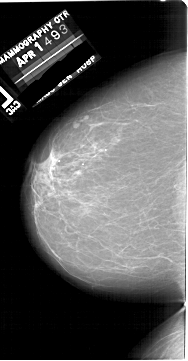

A_1747_1.RIGHT_CC

LEFT_CC LINES 6481 PIXELS_PER_LINE 3376 BITS_PER_PIXEL 12 RESOLUTION 43.5 NON_OVERLAY